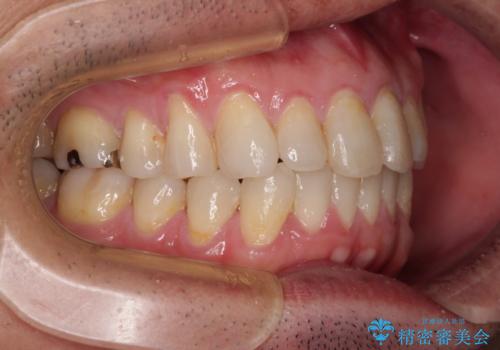

内側に転位した歯とボロボロのむし歯 インビザラインによる矯正治療とむし歯治療

- ボロボロのむし歯とデコボコの歯列を気にして来院された患者様です。

ボロボロとなっていた歯は抜歯が必要な状態でしたが、舌側転位している歯を移動させることで抜歯スペースを埋めることができるため、矯正治療により歯列を整えることとしました。

舌側転位の改善にインビザラインを用いるのはやや難易度が高くなりますが、前歯部のデコボコは軽度であったため、インビザラインによる矯正治療を行うこととしました。